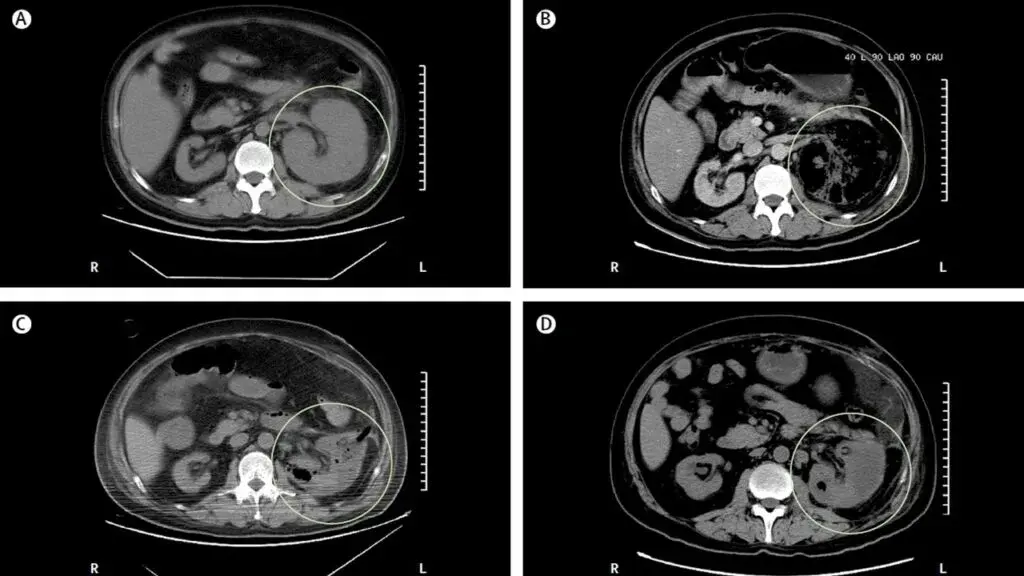

Caso típico de **pielonefritis enfisematosa** publicado en The Lancet ([link](https://www.thelancet.com/journals/lancet/article/PIIS0140-6736(19)30771-8/fulltext)). Los casos generalmente son resultado de una infección por *Escherichia coli* en pacientes con diabetes descompensada y obstrucción del tracto urinario. La glucosa es un sustrato para la proliferación de bacterias fermentadoras (*Enterobacteriaceae*) que producen dióxido de carbono e hidrógeno. **Es importante destacar el alto riesgo de embolización**. Cuando hay obstrucción presente, es obligatorio desobstruir la vía urinaria. En casos con gas en el parénquima o espacio perirrenal, se sugiere fuertemente la drenaje percutáneo. Si el gas se limita al espacio colector (pielitis aislada), el tratamiento con antibióticos es suficiente.